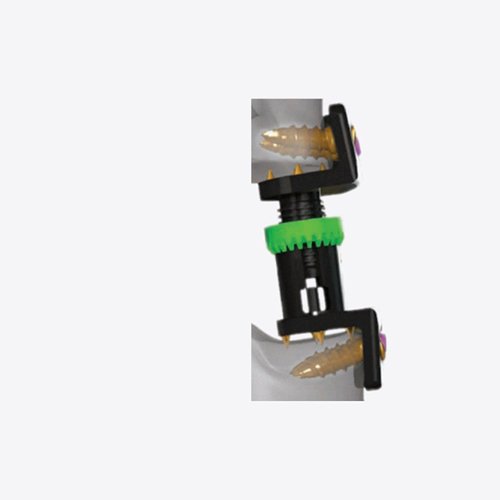

The Duo – Anterior Cervical Cage is an innovative, all-in-one interbody fusion device designed for use in Anterior Cervical Discectomy and Fusion (ACDF) procedures. Engineered for both fusion support and anterior fixation, the Duo Cage eliminates the need for a separate plate, streamlining surgery while maintaining biomechanical integrity and cervical spine alignment.

12 x 15 x 7°

Size : 5mm to 11mm (1mm Variation)